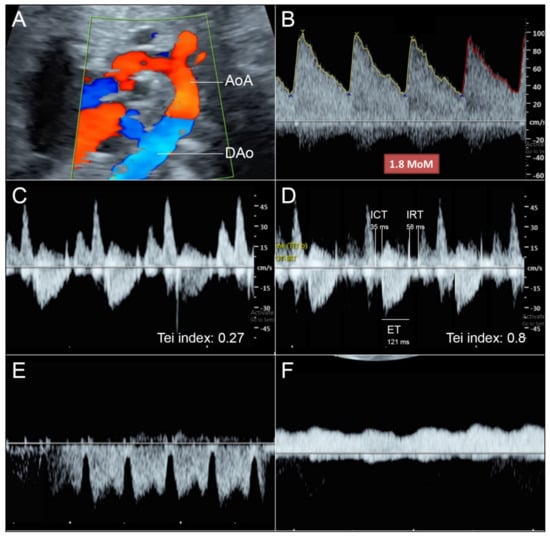

- Reversed flow in aortic arch is commonly seen in hypoplastic left heart or aortic stenosis but in this case the flow crossing the aortic valve shows normal laminar flow.

- Reversed flow in aortic arch is different from that seen in fetal growth restriction (FGR), which usually shows increased afterload (abnormal umbilical blood flow).